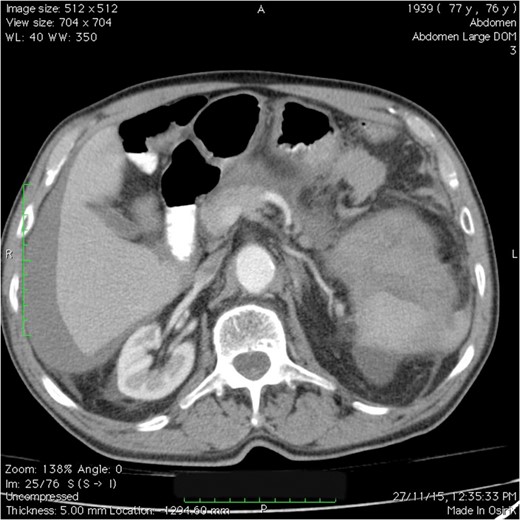

CT scan of the abdomen and pelvis: splenic injury with a large amount of blood in the left upper quadrant, perihepatic region and pelvic areas.

CT scan is highly accurate for detecting splenic injury and the extent of hemoperitoneum. This examination is considered the diagnostic modality of choice in a stable patient [7]. Although splenectomy is required in the majority of cases, observation or splenorrhaphy may represent alternative options for the surgeon in certain cases. The non-operative approach is usually preferred in patients with no intraperitoneal blood, a closed subcapsular hematoma and a stable hemodynamic status [3].